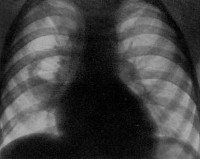

При подозрении на стафилококковую пневмонию проводятся повторные рентгенографии легких через короткие интервалы. На ранней стадии обнаруживаются признаки неспецифической бронхопневмонии. Стафилококковые инфильтраты видны как негомогеннные полиморфные области затемнения, обычно на границах легочных сегментов. После формирования абсцессов в области очага инфильтрации выявляются полости с горизонтальным уровнем жидкости. В случае метастатической деструкции легких полости с жидким содержимым и перифокальной инфильтрацией сочетаются с воздушными полостями, не имеющими стенок.